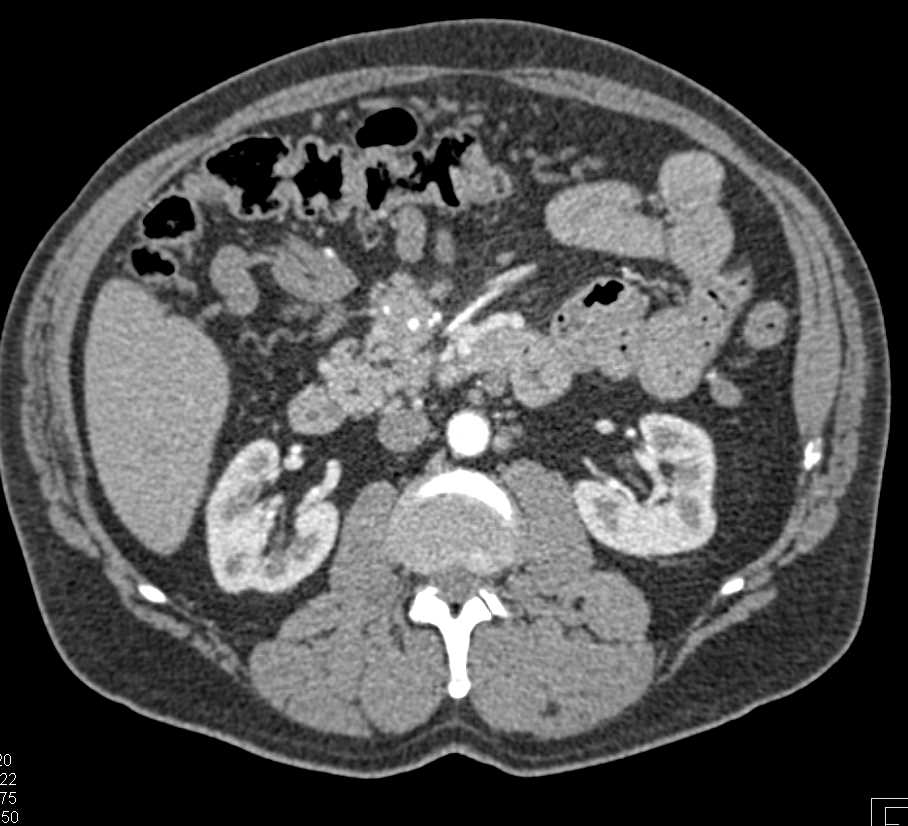

Small Bowel Obstruction (SBO) due to Inguinal Hernia with Pneumoperitoneum